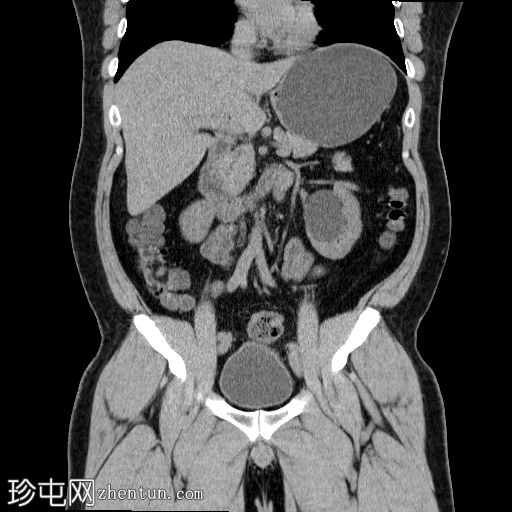

矢状位

平扫

左侧肾盂输尿管连接部(PUJ)可见一枚较大的不透射线结石,最大直径达24 mm,平均CT值约为1160 HU。该结石引起反压改变,导致明显的左肾积水。

此外,左肾中极肾盏内可见一枚直径约13 mm的非梗阻性不透射线结石,平均CT值为1100 HU。

另外,左肾下极肾盏内可见多枚聚集性不透射线结石,总直径约20 mm,平均CT值约为1140 HU。

输尿管肾盂交界处(PUJ)梗阻是肾积水的常见原因,可以是先天性的,也可以是后天性的。在成人中,最常见的原因是梗阻性结石,正如本病例所示。

密度值(>1100 HU)提示草酸钙或混合钙结石,这类结石通常质地较硬,体外冲击波碎石术(ESWL)难以将其击碎,因此通常需要其他介入治疗,例如输尿管镜检查、经皮肾镜取石术或手术治疗。